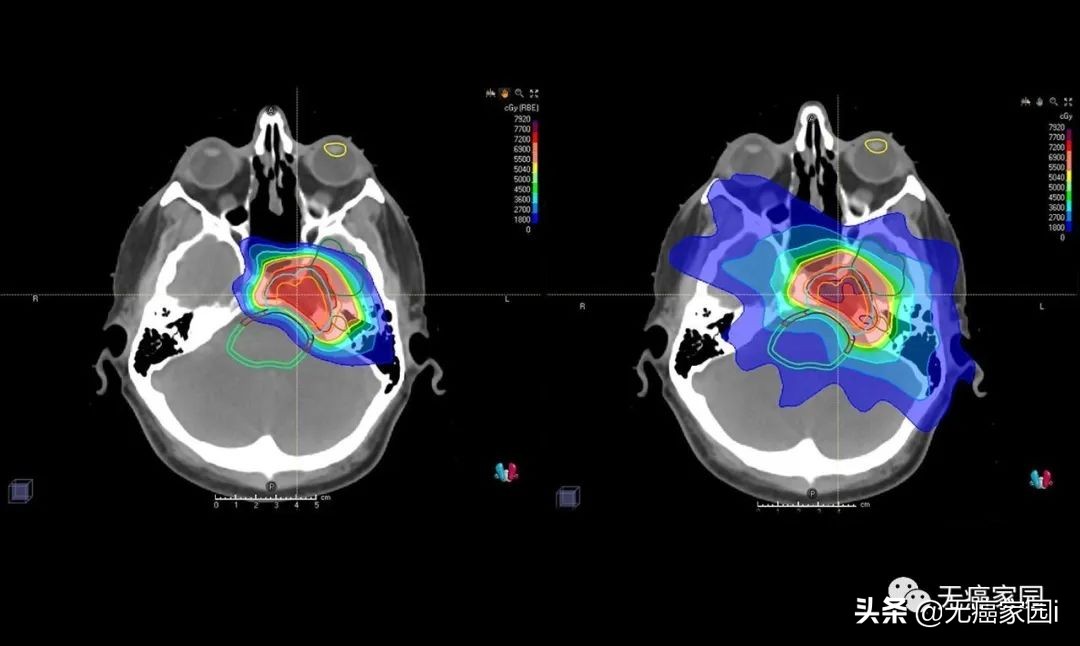

图中患者的脑部扫描显示质子(左)如何专门针对肿瘤,而对周围组织和结构的辐射最小,传统的光子辐射(右)会损坏周围的组织和结构